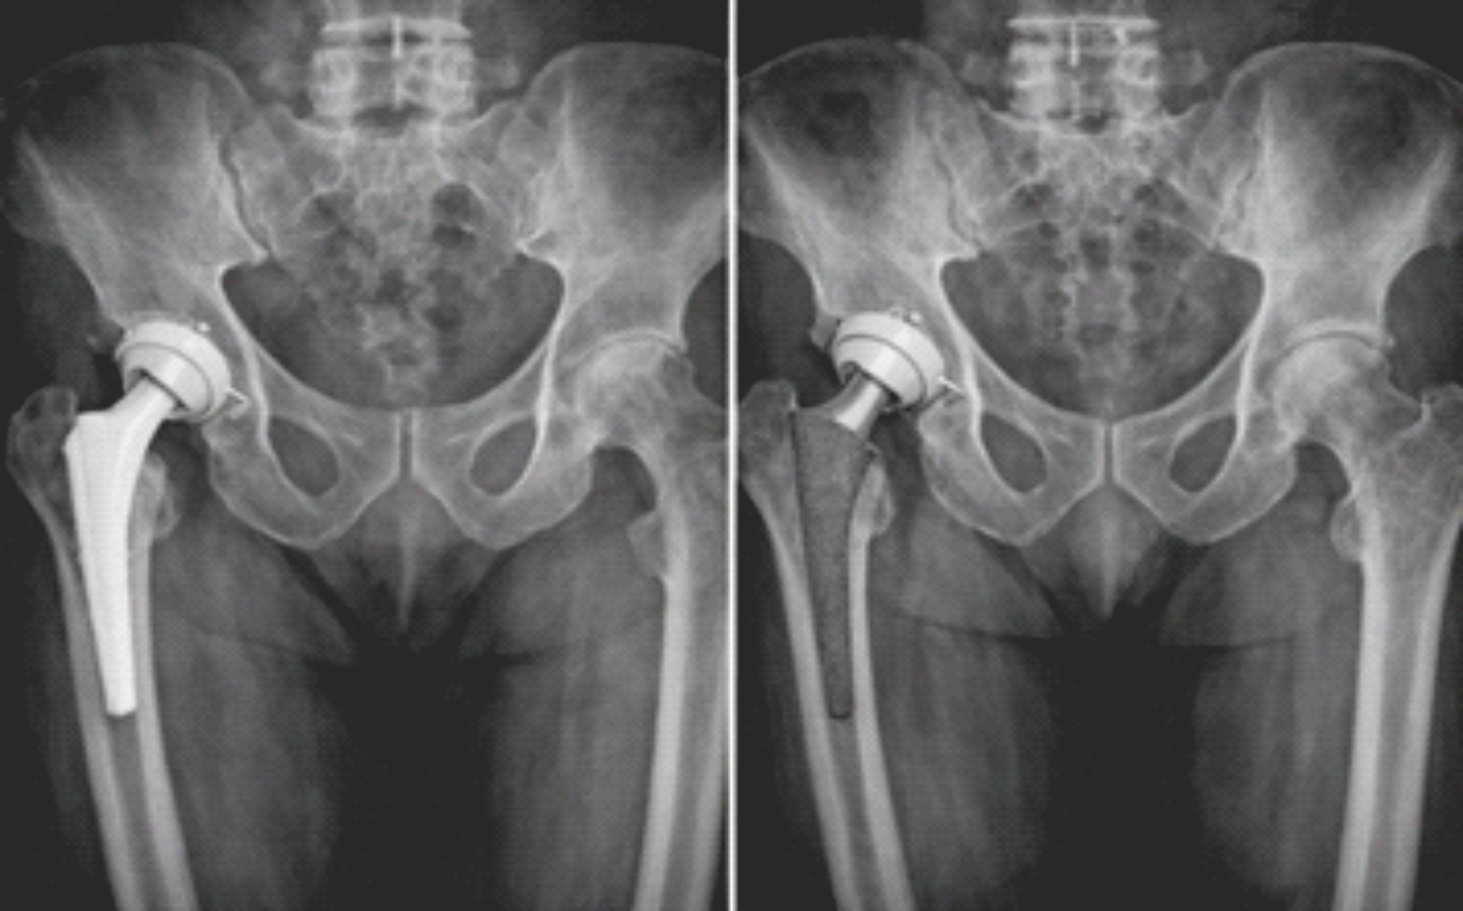

At final follow-up, radiographic evaluation revealed a low incidence of femoral stem subsidence and radiolucent lines in both groups. Stem subsidence >2 mm was more commonly observed in the cementless THA group, though the difference was not statistically significant. The majority of implants in both groups demonstrated satisfactory alignment on radiographs, with no significant intergroup difference (Table 5 and Fig. 1).

Figure 1: Anteroposterior pelvic radiograph comparing a cemented femoral stem (left) to a cementless femoral stem in direct bone contact (right).